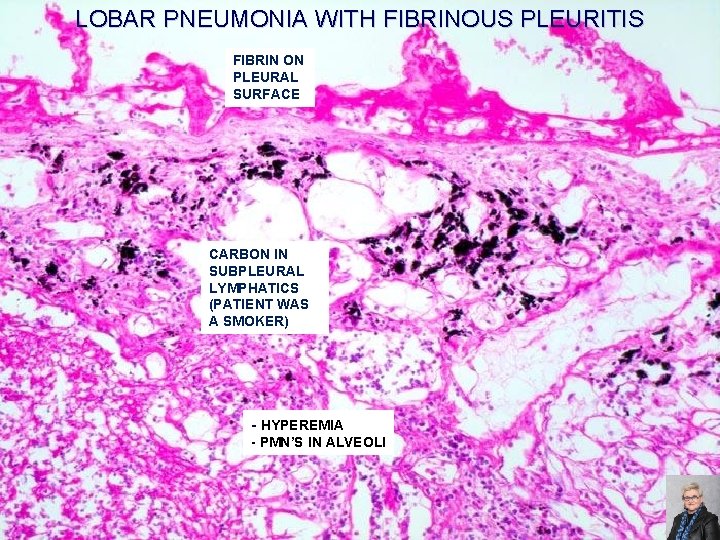

LOBAR PNEUMONIA WITH FIBRINOUS PLEURITIS FIBRIN ON PLEURAL SURFACE CARBON IN SUBPLEURAL LYMPHATICS (PATIENT WAS A SMOKER) - HYPEREMIA - PMN’S IN ALVEOLI 66